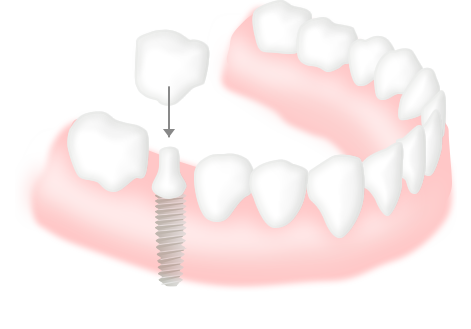

インプラントの構造は右の図のように、上部構造・アバットメント・インプラント体(人工歯根)の大きく3つの部位に分けられます。歯を失った骨にインプラントを埋め込み、その上に歯を立ち上げます。歯の欠損が与える影響は、機能・審美・そして精神的にも大きなダメージです。インプラント治療は、歯の欠損における有効な治療法ですが、近年では審美性の回復も可能となる治療へとさらに発展しつつあります。

インプラント

健康な歯はそのままに、インプラントを埋め込み、1本の人工の歯冠を固定します。

- 健康な歯を維持できる

- 歯根があるので正しい力が加わり歯茎も健康に保てる

- 天然の歯と変わらない外観と機能が保てる